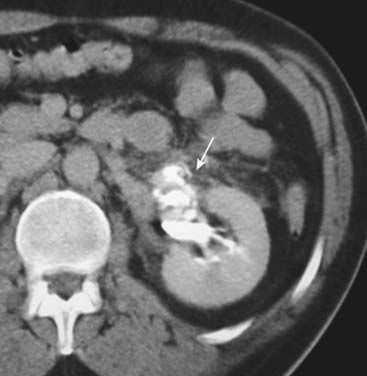

image CT findings in renal trauma (Fig. 17-9):

Laceration. Low-attenuation linear or branching defects in the renal parenchyma. More severe lacerations may extend through the renal hilum into the collecting system, renal artery, or vein. “Fracture” is a term that may be used when the laceration connects the hilum with the cortex.

image

Figure 17-9 Renal trauma, two different patients.

A, Coronal-reformatted, contrast-enhanced CT scan shows a low-attenuation linear defect representing a renal laceration (solid black arrow) and a subcapsular hematoma (solid white arrow). B, Axial CT scan on another patient also shows a renal laceration (solid black arrow) and a perinephric hematoma (dotted black arrow).